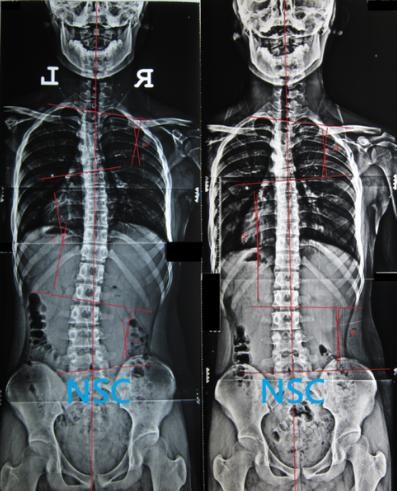

case:2